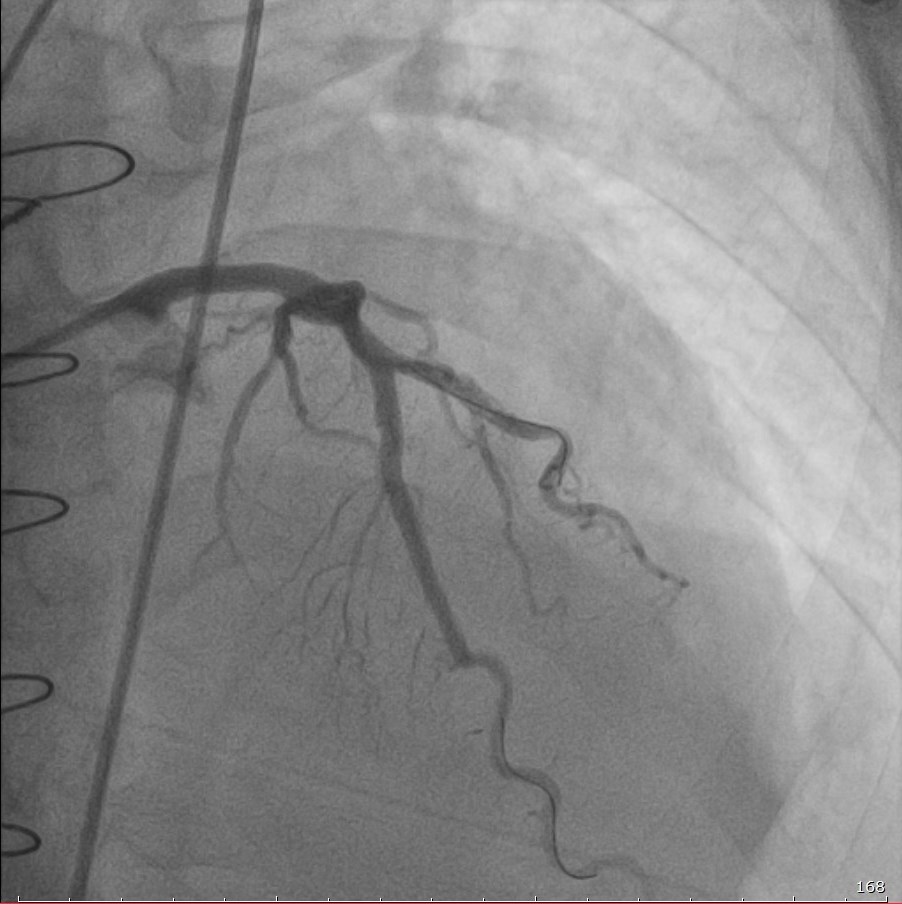

С учётом сложности случая и ранее установленного стента врачи ГКБСМП провели телемедицинскую консультацию с федеральным центром. По рекомендациям специалистов выполнена коронарография и начата гормональная терапия. В ходе вмешательства пациенту имплантированы три стента с лекарственным покрытием, что позволило предотвратить инфаркт и купировать признаки отторжения.